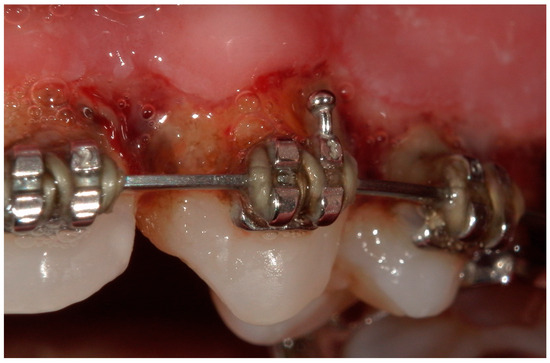

4. Clinical Cases

4.1. Case 1

4.2. Case 2